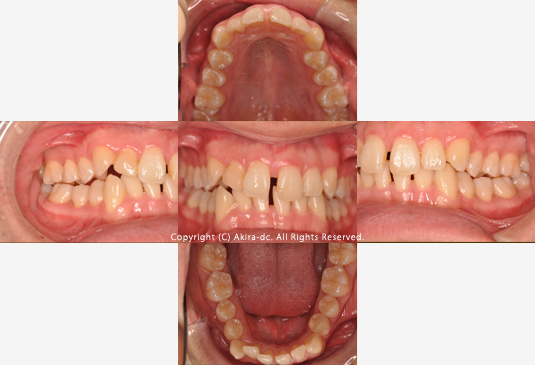

下の犬歯(糸切り歯)の位置、下の前歯の歯並びが気になるとのことでご相談頂きました。

右下の3番目の歯(犬歯、糸切り歯)が歯列から外に出ていて、残念ながら3番目の歯の入るスペースが不足していました。また、上下の歯列の形がきれいな楕円形ではなく、舌の動きを妨げてしまうような狭い歯列になっています。

初診時口腔内写真

下の犬歯(糸切り歯)の位置が気になるとのことでご相談頂きました。

術前 正面写真 |

1年9ヶ月経過 正面写真 |